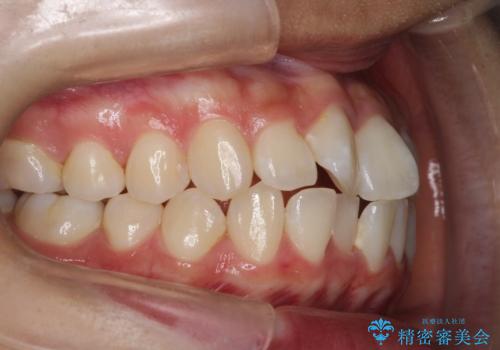

前歯のがたがたを綺麗にしたい

- 前歯がねじれていること、出ていることを主訴に来院されました。

前歯の突出感も改善され、満足していただきました。